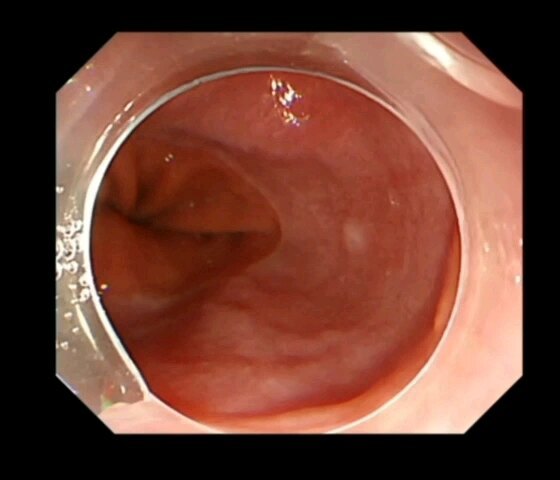

越来越多的健康人群开始重视胃肠镜体检,有些人拿到报告后,在胃镜检查报告中,发现有胃“SMT”的字样,很紧张,甚至以为自己得了什么绝症。今天,我们就简单来介绍一下胃SMT。SMT意思是消化道黏膜下肿瘤(SubMucosalTumor,SMT)。这是指一类来自消化道黏膜以下组织的肿块,包括起源于黏膜肌层、黏膜下层和固有肌层的肿瘤。它们在内镜下的表现形态相似,即表面覆有正常黏膜的隆起性病变,医生一般不取活检,因为活检取不到黏膜下的组织。发现SMT后,可能会被要求做个超声内镜(EndoscopicUltrasonography,EUS),有的时候会联合消化道增强CT,以确定肿瘤的来源层次、大小、质地及与周边组织血管的毗邻关系。上消化道的SMT以食管和胃最为常见,十二指肠较少见。最常见的上消化道SMT包括平滑肌瘤、间质瘤、神经内分泌肿瘤、脂肪瘤、颗粒细胞瘤、神经鞘瘤等。非肿瘤性病变的异位胰腺也会表现为SMT样。 胃黏膜下肿瘤发病率约十万分之一。患者很少有症状,大部分是因为体检胃镜无意中发现。如果肿瘤持续长大,影响食物通过或者表面有糜烂破溃时,则会出现疼痛、消化道出血等不适。那么发现了胃黏膜下肿瘤,到底是否需要切除呢,一般来说小于1cm的SMT,建议随访。当出现以下这些情况时,建议切除: 1)有症状(伴有出血、消化道梗阻等); 2)无症状但不断增大的黏膜下肿瘤; 3)明确是胃间质瘤(有恶性潜能,随直径增大恶性潜能增大); 4) 肿瘤大于2cm怀疑是胃间质瘤; 5) 性质不明确的黏膜下肿瘤,但是不能耐受或者因为焦虑不愿长期内镜检查随访。胃镜下手术创伤小,恢复快,是较小的黏膜下肿瘤治疗的优选(一般来说小于5cm的间质瘤,像平滑肌瘤更大也可以内镜下切除),可以完整切除后病理检查明确肿瘤性质内镜下的手术方式包括内镜黏膜下剥离术(ESD)、内镜黏膜下挖除术(ESE)、内镜全层切除术(EFTR)和内镜经黏膜下隧道肿瘤切除术(STER)。胃镜发现的SMT是胃癌吗?如何治疗?段本松 东方内镜 2024年07月27日17:40 上海 12人胃镜发现的SMT是胃癌吗?如何治疗?徐美东消化内镜工匠创新工作室科普系列文章越来越多的健康人群开始重视胃肠镜体检,有些人拿到报告后,在胃镜检查报告中,发现有胃“SMT”的字样,很紧张,甚至以为自己得了什么绝症。今天,我们就简单来介绍一下胃SMT。SMT意思是消化道黏膜下肿瘤(SubMucosalTumor,SMT)。这是指一类来自消化道黏膜以下组织的肿块,包括起源于黏膜肌层、黏膜下层和固有肌层的肿瘤。它们在内镜下的表现形态相似,即表面覆有正常黏膜的隆起性病变,医生一般不取活检,因为活检取不到黏膜下的组织。发现SMT后,可能会被要求做个超声内镜(EndoscopicUltrasonography,EUS),有的时候会联合消化道增强CT,以确定肿瘤的来源层次、大小、质地及与周边组织血管的毗邻关系。上消化道的SMT以食管和胃最为常见,十二指肠较少见。最常见的上消化道SMT包括平滑肌瘤、间质瘤、神经内分泌肿瘤、脂肪瘤、颗粒细胞瘤、神经鞘瘤等。非肿瘤性病变的异位胰腺也会表现为SMT样。 胃黏膜下肿瘤发病率约十万分之一。患者很少有症状,大部分是因为体检胃镜无意中发现。如果肿瘤持续长大,影响食物通过或者表面有糜烂破溃时,则会出现疼痛、消化道出血等不适。那么发现了胃黏膜下肿瘤,到底是否需要切除呢,一般来说小于1cm的SMT,建议随访。当出现以下这些情况时,建议切除: 1)有症状(伴有出血、消化道梗阻等); 2)无症状但不断增大的黏膜下肿瘤; 3)明确是胃间质瘤(有恶性潜能,随直径增大恶性潜能增大); 4) 肿瘤大于2cm怀疑是胃间质瘤; 5) 性质不明确的黏膜下肿瘤,但是不能耐受或者因为焦虑不愿长期内镜检查随访。胃镜下手术创伤小,恢复快,是较小的黏膜下肿瘤治疗的优选(一般来说小于5cm的间质瘤,像平滑肌瘤更大也可以内镜下切除),可以完整切除后病理检查明确肿瘤性质内镜下的手术方式包括内镜黏膜下剥离术(ESD)、内镜黏膜下挖除术(ESE)、内镜全层切除术(EFTR)和内镜经黏膜下隧道肿瘤切除术(STER)。接下来,我将结合我中心的实际临床病例,为大家介绍最常见的两种胃镜下发现的SMT:平滑肌瘤、间质瘤。01食管胃平滑肌瘤平滑肌瘤(Leiomyoma)是一种良性间叶肿瘤,具有平滑肌分化特征。胃镜发现的平滑肌瘤主要分布在食管和胃,尤其以食管为主,常见于食管胃交界处和食管中部。大多数患者无症状,当肿瘤增大时可能出现吞咽困难、疼痛或不适,常见的主诉包括胸骨后、剑突下或上腹部的疼痛或不适,以及上腹部饱胀感或压迫感。其他消化道非特异性症状包括食欲不振、反胃、嗳气、恶心和呕吐等。目前,内镜下对平滑肌瘤的诊断及处理已经非常成熟。病例1:食管平滑肌瘤患者女,37岁,外院胃镜检查发现食管距门齿35cm-37cm处有一黏膜下隆起,遂来我院行超声内镜检查。检查提示隆起处有均匀低回声团块,边界清晰,回声与固有肌层连续,截面大小约2.02.0cm,结合CT报告考虑平滑肌瘤可能。我中心决定采用内镜经黏膜下隧道肿瘤切除术(STER)进行肿瘤切除,手术顺利取出大小约2.5cm的平滑肌瘤。病例2:胃近贲门平滑肌瘤患者女,55岁,1年前当地医院胃镜检查发现胃底黏膜下隆起,未予重视,未服药及规范随访。近日复查内镜发现胃底黏膜下隆起较之前增大,遂来我院诊治。CT提示贲门占位,大小约4.0cm。结合超声胃镜结果,考虑贲门SMT,平滑肌瘤可能。我中心决定采用STER进行肿瘤切除,手术顺利,取出大小约4.0cm的马蹄样平滑肌瘤。胃镜发现的SMT是胃癌吗?如何治疗?段本松 东方内镜 2024年07月27日17:40 上海 12人胃镜发现的SMT是胃癌吗?如何治疗?徐美东消化内镜工匠创新工作室科普系列文章越来越多的健康人群开始重视胃肠镜体检,有些人拿到报告后,在胃镜检查报告中,发现有胃“SMT”的字样,很紧张,甚至以为自己得了什么绝症。今天,我们就简单来介绍一下胃SMT。SMT意思是消化道黏膜下肿瘤(SubMucosalTumor,SMT)。这是指一类来自消化道黏膜以下组织的肿块,包括起源于黏膜肌层、黏膜下层和固有肌层的肿瘤。它们在内镜下的表现形态相似,即表面覆有正常黏膜的隆起性病变,医生一般不取活检,因为活检取不到黏膜下的组织。发现SMT后,可能会被要求做个超声内镜(EndoscopicUltrasonography,EUS),有的时候会联合消化道增强CT,以确定肿瘤的来源层次、大小、质地及与周边组织血管的毗邻关系。上消化道的SMT以食管和胃最为常见,十二指肠较少见。最常见的上消化道SMT包括平滑肌瘤、间质瘤、神经内分泌肿瘤、脂肪瘤、颗粒细胞瘤、神经鞘瘤等。非肿瘤性病变的异位胰腺也会表现为SMT样。 胃黏膜下肿瘤发病率约十万分之一。患者很少有症状,大部分是因为体检胃镜无意中发现。如果肿瘤持续长大,影响食物通过或者表面有糜烂破溃时,则会出现疼痛、消化道出血等不适。那么发现了胃黏膜下肿瘤,到底是否需要切除呢,一般来说小于1cm的SMT,建议随访。当出现以下这些情况时,建议切除: 1)有症状(伴有出血、消化道梗阻等); 2)无症状但不断增大的黏膜下肿瘤; 3)明确是胃间质瘤(有恶性潜能,随直径增大恶性潜能增大); 4) 肿瘤大于2cm怀疑是胃间质瘤; 5) 性质不明确的黏膜下肿瘤,但是不能耐受或者因为焦虑不愿长期内镜检查随访。胃镜下手术创伤小,恢复快,是较小的黏膜下肿瘤治疗的优选(一般来说小于5cm的间质瘤,像平滑肌瘤更大也可以内镜下切除),可以完整切除后病理检查明确肿瘤性质内镜下的手术方式包括内镜黏膜下剥离术(ESD)、内镜黏膜下挖除术(ESE)、内镜全层切除术(EFTR)和内镜经黏膜下隧道肿瘤切除术(STER)。接下来,我将结合我中心的实际临床病例,为大家介绍最常见的两种胃镜下发现的SMT:平滑肌瘤、间质瘤。01食管胃平滑肌瘤平滑肌瘤(Leiomyoma)是一种良性间叶肿瘤,具有平滑肌分化特征。胃镜发现的平滑肌瘤主要分布在食管和胃,尤其以食管为主,常见于食管胃交界处和食管中部。大多数患者无症状,当肿瘤增大时可能出现吞咽困难、疼痛或不适,常见的主诉包括胸骨后、剑突下或上腹部的疼痛或不适,以及上腹部饱胀感或压迫感。其他消化道非特异性症状包括食欲不振、反胃、嗳气、恶心和呕吐等。目前,内镜下对平滑肌瘤的诊断及处理已经非常成熟。病例1:食管平滑肌瘤患者女,37岁,外院胃镜检查发现食管距门齿35cm-37cm处有一黏膜下隆起,遂来我院行超声内镜检查。检查提示隆起处有均匀低回声团块,边界清晰,回声与固有肌层连续,截面大小约2.02.0cm,结合CT报告考虑平滑肌瘤可能(图1)。我中心决定采用内镜经黏膜下隧道肿瘤切除术(STER)进行肿瘤切除,手术顺利取出大小约2.5cm的平滑肌瘤(图2)。病例2:胃近贲门平滑肌瘤患者女,55岁,1年前当地医院胃镜检查发现胃底黏膜下隆起,未予重视,未服药及规范随访。近日复查内镜发现胃底黏膜下隆起较之前增大,遂来我院诊治。CT提示贲门占位,大小约4.0cm。结合超声胃镜结果,考虑贲门SMT,平滑肌瘤可能(图3)。我中心决定采用STER进行肿瘤切除,手术顺利,取出大小约4.0cm的马蹄样平滑肌瘤(图4)。02胃肠道间质瘤胃肠道间质瘤(GIST)是消化道最常见的间叶源性肿瘤,约占全消化道肿瘤的3%。在消化道中,以胃最为常见,其他部位较少见。因此,胃镜下发现的间质瘤大多位于胃部。该肿瘤可发生于任何年龄。男女发病差异不明显。早期多无症状,由于其球状非侵袭性的生长方式,即便肿瘤较大也不一定产生压迫感和出血,是一种很难在早期发现的隐形杀手。随着内镜检查的普及和技术进步,早期发现和超级微创治疗GIST已经成为可能。内镜下的超级微创手术治疗GIST不仅创伤小、痛苦少、操作时间短、并发症少,还能提供完整的病理学诊断资料,以便制定预后和随访策略。病例3:胃底间质瘤患者女,76岁,半年前体检时胸部CT平扫提示胃底可疑占位。病程中,患者偶有反酸,无其他不适。再次复查胸部CT提示胃底可疑占位,超声胃镜显示病灶呈均匀低回声,边界清楚,起源于固有肌层,大小约26mm24mm,结合CT报告考虑间质瘤伴钙化可能。我中心决定采用内镜全层切除术(EFTR)进行肿瘤切除,手术顺利取出大小约3.5cm的间质瘤。总之,胃镜检查发现胃SMT后,无需过分紧张,需要寻求专业的内镜医生意见,随访或内镜下切除,如果较大无法内镜下切除则需要考虑外科手术治疗。